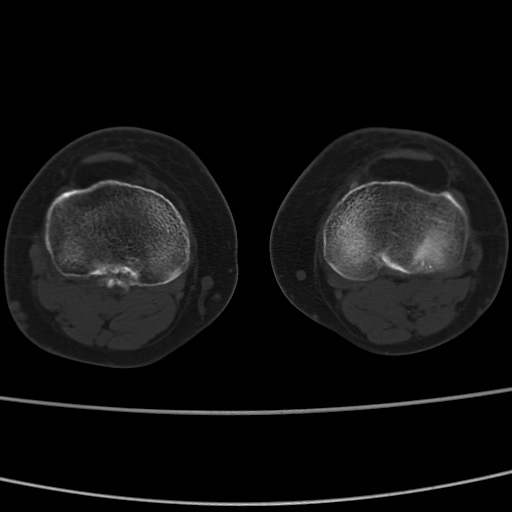

女性,50岁。【请提供患者临床症状体征】

右膝关节退行性改变,关节游离鼠。

右膝关节退行性改变,滑膜黏液囊钙/骨化并游离。

右膝关节退行性改变